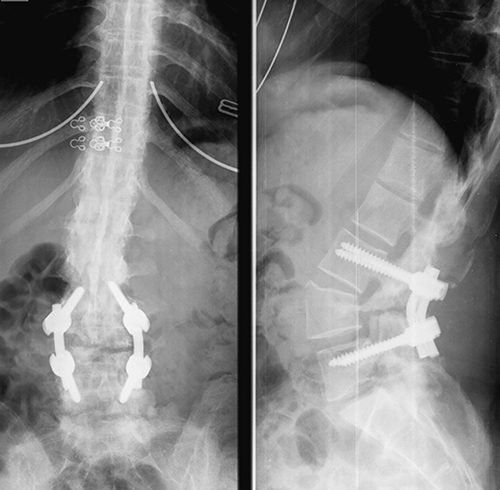

2014 թվականի նոյեմբերի 4-ին «Էրեբունի» բժշկական կենտրոնի նյարդաբանության կլինիկայի ղեկավար, բ. գ. դ., պրոֆեսոր Մ.Ա. Եղունյանի և նույն կենտրոնի ողնաշարային ախտաբանության ծառայության ղեկավար Կ.Գ. Մոմջյանի ղեկավարությամբ իրականացվել է 1976թ. ծնված հիվանդ Մ.Ա.՝ Բեխտերևի հիվանդության արդյունքում առաջացած ողնաշարի ձևախախման վիրաբուժական ուղղման հաջող վիրահատությունը` IV գոտկային ողի պեդիկուլյար սուբտրակցիոնային օստեոտոմիա նյարդադիտարկումային վերահսկման տակ: Վերջինս վիրահատության ամբողջ ընթացքում ապահովում է ողնուղեղի մշտական հսկողությունը՝ այդպիսով նվազեցնելով ողնուղեղի վնասման հավանականությունը հատկապես ձևախախտման ուղղման պահին:

![]() |

Բուժման ժամանակակից մեթոդները թույլ են տալիս վիրաբուժական միջամտությամբ ուղղել ողնաշարի ձևախախտումները: Երկու տեսակի վիրահատական միջամտություն է իրականացվում. 1. Ողերի հետին տարրերի ոսկրահատում ըստ Սմիթ-Պետերսոնի և 2. ողնաշարի պեդիկուլյար սուբտրակցիոն ոսկրահատում: Առաջին վիրահատությունն առավել կիրառելի է թույլ արտահայտված ձևախախտումների ժամանակ, իսկ երկրորդ վիրահատության իմաստը գոտկային II, III կամ IV ողերի առաջային և հետին տարրերի սեպաձև հեռացումն է՝ ողնաշարի ձևախախտուման շարժունացմամբ, տրանսպեդիկուլյար իմպլանտների տեղադրմամբ, որոնց օգնությամբ իրականացվում է մոբիլիզացված ձևախախտումների ուղղումը և գոտկային լորդոզի ստեղծումը: Սա թույլ է տալիս հասնել պացիենտի մարմնի ուղղաձիգ դիրքին: Վիրահատությունից հետո հիվանդները կարող են ոտքի կանգնել 2-7 օրերի ընթացքում և կարիք չունեն արտաքին կորսետների:

Այս տեսակի վիրահատությունները ողնաշարի վրա իրականացվող վիրահատություններից բարդագույններից են համարվում: Հայաստանում նման վիրահատություն իրականացվում է երկրորդ անգամ: Առաջինը մեկ տարի առաջ ևս իրականացվել է մեր հիվանդանոցում: